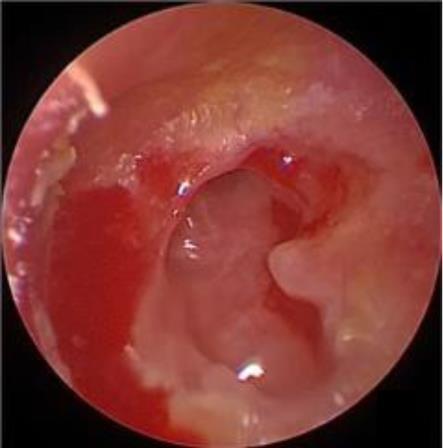

摘要:目的 探究经中鼻甲基板入路的手术技巧及临床效果,旨在系统评估一种兼具良好手术视野和微创性的蝶窦开放径路。方法 回顾性分析2019年9月-2023年9月该院收治的35例孤立性蝶窦病变或单侧蝶窦伴毗邻筛窦受累患者的临床资料,均经中鼻甲基板入路的“四步”程序化操作开放蝶窦。观察手术相关情况和并发症发生情况;采用视觉模拟评分法(VAS)评分,评估头痛和流涕等症状改善情况;采用改良隆德-肯尼迪(MLK)评分,评价术腔恢复状况。结果 所有患者术中保留钩突、中鼻甲和筛泡,26例(74.3%)保留上鼻甲;所有患者均达到临床治愈标准,表现为:术腔引流通畅,黏膜完全上皮化,以及蝶窦开口维持良好开放状态。术后病理显示:蝶窦霉菌病19例(54.3%),蝶窦息肉7例(20.0%),蝶窦黏膜慢性炎症9例(25.7%)。所有患者均未发生严重并发症,仅1例(2.9%)于术后12 d出现中鼻甲创面渗血,经电凝止血后治愈。头痛VAS评分由术前的(4.71±1.66)分,降至术后的(0.83±0.39)分,手术前后比较,差异有统计学意义(t = 13.71,P < 0.01);流涕VAS评分由术前的4.00(0.00,6.00)分,降至术后的0.00(0.00,1.00)分,手术前后比较,差异有统计学意义(Z = -4.47,P < 0.01);手术前后嗅觉减退VAS评分比较,差异无统计学意义(P > 0.05)。MLK评分由术前的4.50(2.00,4.00)分降至1.00(0.00,1.00)分,手术前后比较,差异有统计学意义(Z = -5.20,P < 0.01)。结论 经中鼻甲基板入路蝶窦开放术,严格遵循鼻窦解剖层次,在最大限度地保留鼻腔生理结构的前提下,可获得理想的术野暴露。该术式对于局限于蝶窦及后组筛窦的病变,具有确切的临床疗效。值得应用于临床。